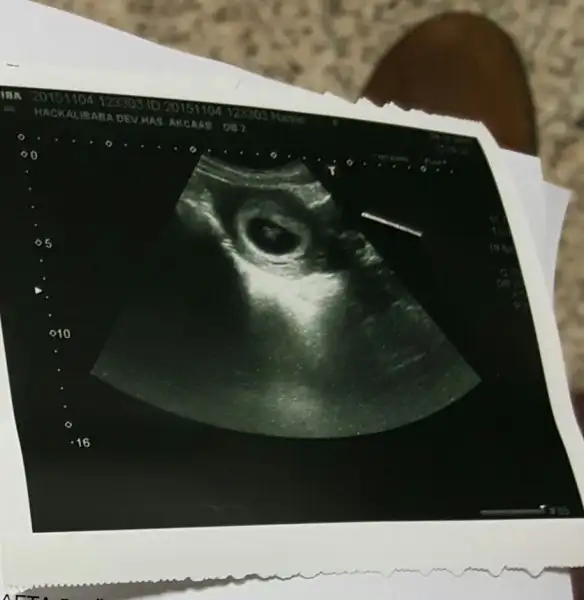

Vajinal ultrason. Gibi yani kibir başka usg resmim

sorum olacaktı acaba bnmki fotoya göre kızmı erkekmi 11 haftalık hamileyim bu ultrason 6 hafta 5 günlübenimki sağdaymış kızım yani:ecrin_bebek:

bir başka usg resmim

hele hamilelik belirtilerim tamamen farklı ilk bebeğim rahmin solunda bu bebişim sağda, ilk hamilelik aşırı bulantılı bunda hiç bulantı yok. oğlumda yüzüm çok güzelleşmişti bunda sivilcelendim. oğlumda süt, peynir et çok yedim, bunda varsa yoksa meyve sebze. sürekli kanamam ve lekelenmem var bu sefer, ilkinde yoktu.

Bende çin takvimi, rus cinsiyet takvimi ,biyoloji takvimde denedim kiz diyor.. arti meyve hic sevmem tatli sevmem tuzlu eksi hic birinide sevmem.. netteki butun belirtilere gore alyans yuzuge kadar hepsinde kiz cikiyor...usg resmindede sagda yani ordada kiz.. ki bende tecrubeli bir anne olarak kiz diyorim. 2 hafta sonra gidecem dr. Bakalim o ne diyecek :))))vallahi benim de erkekse şayet çin takvimleri (her çeşidine baktım), alyans testi, adını unuttum bir arkadaş paylaşmıştı bir test vardı işte o, hepsinde kız diyor hepsi yalan o zaman bacım.